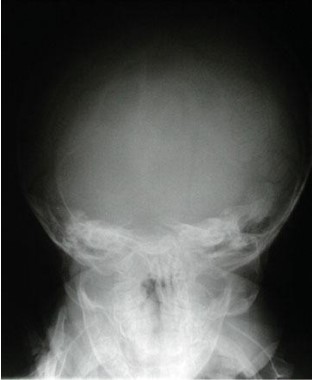

Sinuses anatomy:

Common X-ray Findings: